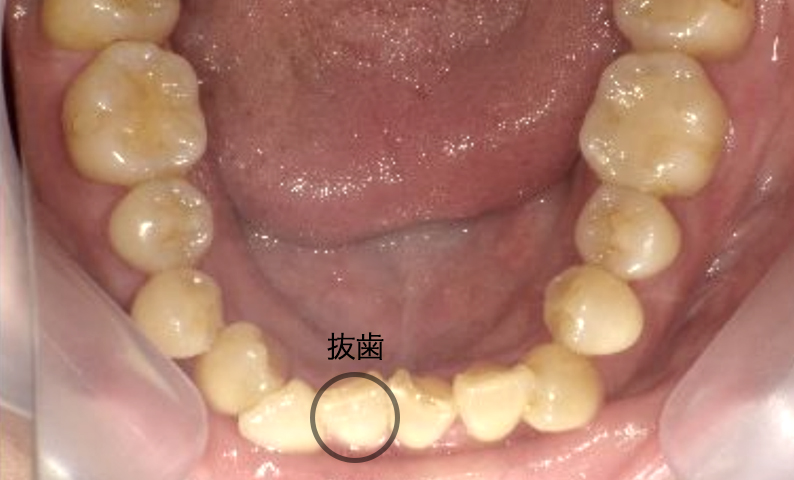

症例_004 下顎だけの部分矯正

治療期間:10ヶ月金額:30万円+税女性前歯のガタガタ下の前歯だけ

| Before | After |